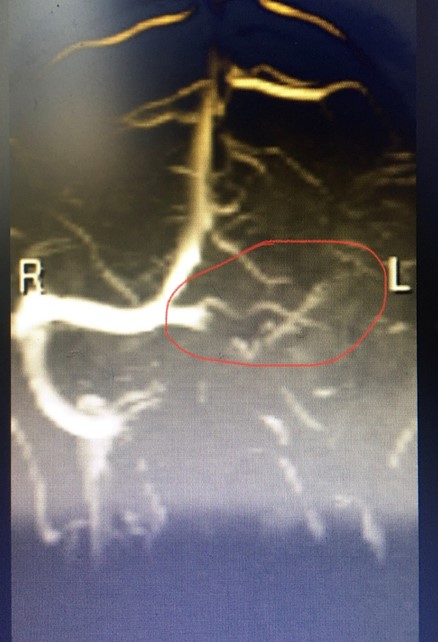

Hình ảnh CLVT và MRI sọ não của bệnh nhân

Trường hợp bệnh nhân nữ 47 tuổi vào Khoa Tâm – thần kinh vì đau đầu sau 02 ngày điều trị tuyến dưới không đỡ. Lúc vào: bệnh nhân tỉnh, đau đầu dữ dội, không có dấu hiệu liệt thần kinh khu trú, không có dấu hiệu màng não, đau đầu tăng dần dùng thuốc giảm đau không đỡ. Bệnh nhân được chụp cắt lớp vi tính sọ não: có hình ảnh dải tăng tỷ trọng nhu mô vùng chẩm bên trái, sau khi thảo luận chúng tôi quyết định chụp cộng hưởng từ não – mạch não thì tĩnh mạch CẤP CỨU, kết quả bệnh nhân bị tắc hoàn toàn xoang tĩnh mạch ngang bên trái. Bệnh nhân đã được đưa về Đơn vị đột quị tiếp tục điều trị ổn định và không để lại biến chứng.